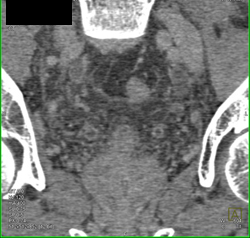

Bladder Cancer